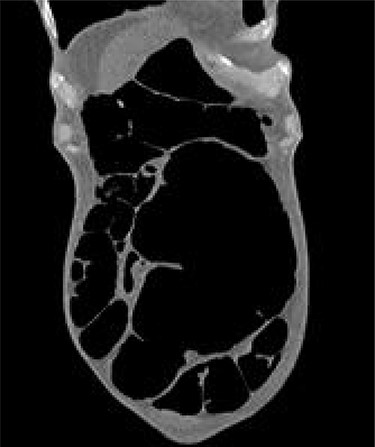

A 54-year-old female presented to the emergency department with a 2-day history of crampy abdominal pain, distension and absolute constipation. She had a history of chronic constipation but no other significant medical history. Her abdomen was diffusely tender and grossly distended on examination, with abdominal X-ray showing the ‘coffee bean’ appearance of SV. Computed tomography (CT) of the abdomen was performed which confirmed the presence of SV without evidence of ischaemia or perforation (Fig. 1). CV was not appreciated on this scan. The patient was brought to the endoscopy unit and underwent sigmoidoscopic decompression. Following this, the patient returned to the ward for observation.

CT appearance suggestive of SV with collapsed right colon and no appreciable CV.